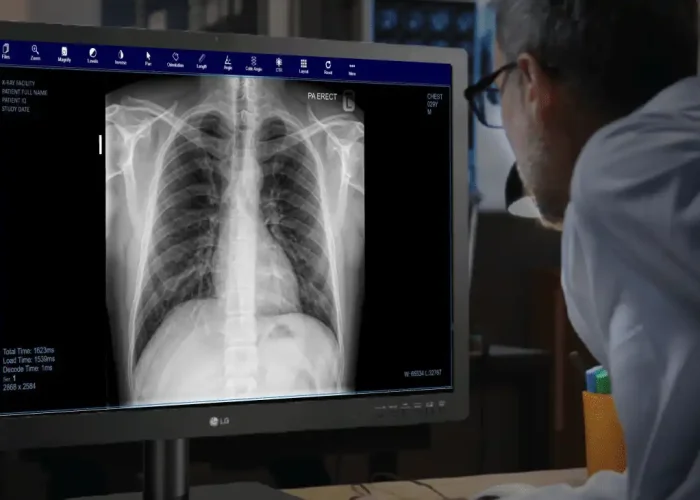

At Awanpro Solutions Sdn. Bhd., we make radiology smarter and more accessible. Our cloud-based teleradiology platform, AMITS (Awanpro Medical Imaging Transmission System), helps hospitals, clinics, and diagnostic centers securely store, share, and report medical images with ease.

We believe healthcare providers should focus on patients, not technology. That’s why our solutions are fast, secure, and easy to use, connecting seamlessly with different X-ray and imaging systems.

At Awanpro Solutions Sdn. Bhd., we make radiology smarter and more accessible. Our cloud-based teleradiology platform, AMITS (Awanpro Medical Imaging Transmission System), helps hospitals, clinics, and diagnostic centers securely store, share, and report medical images with ease.

We believe healthcare providers should focus on patients, not technology. That’s why our solutions are fast, secure, and easy to use, connecting seamlessly with different X-ray and imaging systems.

Our Mission

The mission at AwanPro Solutions is to make advanced diagnostic services accessible to all, bridging the gap between patients and top-tier medical expertise.

AwanPro Solutions' CEO emphasizes, "We're committed to bringing advanced diagnostic services to underserved regions. AMITS is helping turn this vision into reality."

Why Choose Our Teleradiology Solution?

Experience fast, reliable, and secure radiology reporting with cloud-based access—designed to support healthcare providers anytime, anywhere.

Receive radiology reports typically within 2 hours, with urgent cases handled first.

Seamlessly connects to any DICOM-ready modality – X-ray, CT, MRI, ultrasound, and more.